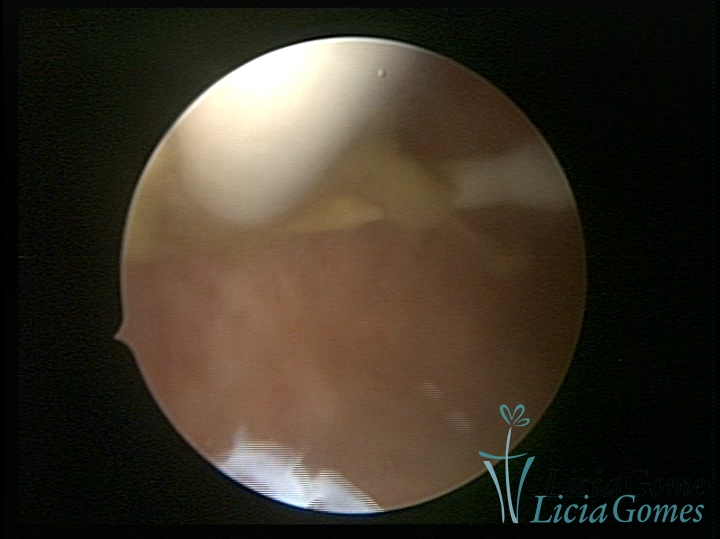

Uterine cavity with IUD